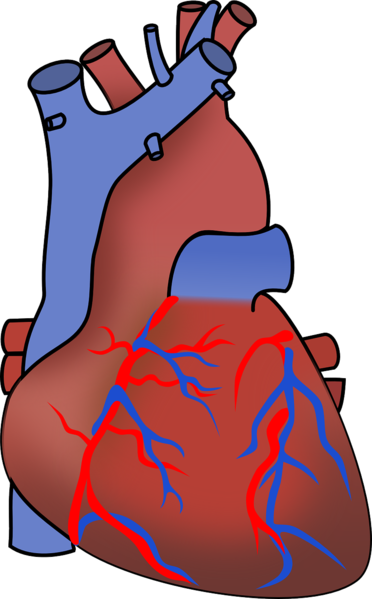

| Beschreibung | Die roten und blauen Verzweigungen sind die Herzkranzarterien. |

| Originaltitel | Human Heart